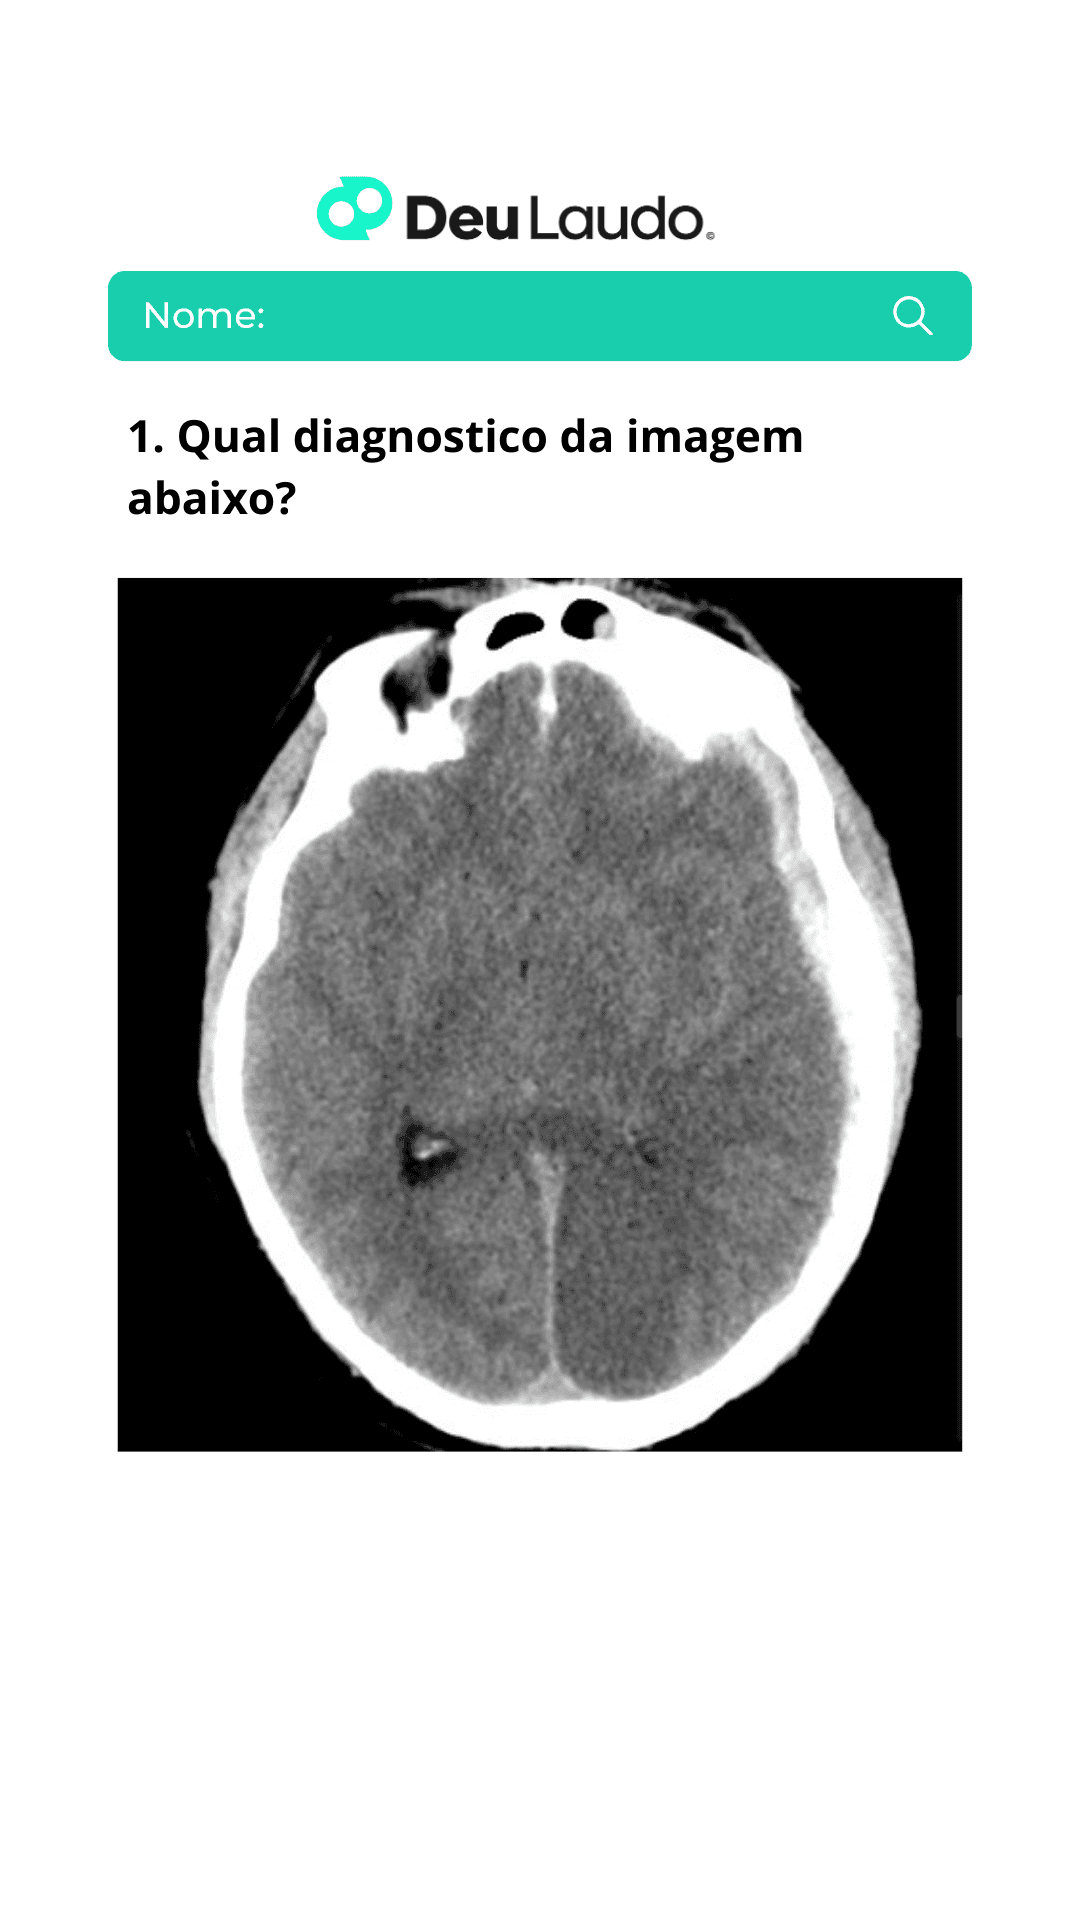

Deu laudo | Pré-r1